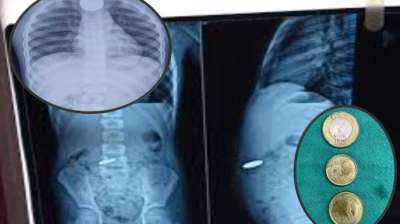

खिलौना नहीं सिक्का था! बच्चे ने निगले 5-10 रुपये के सिक्के, डॉक्टरों ने ऑपरेशन कर निकाले

दिल्ली : दिल्ली के एक सरकारी अस्पताल के डॉक्टरों ने 12 वर्षीय बच्चे की जान बचाई है। बच्चे ने पांच और दस रुपये के तीन सिक्के निगल लिए थे। सिक्के...